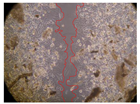

| 2 h | 8 h | 12 h | 24 h | |

| Control | ![]() | ![]() | ![]() | ![]() |

| Samples | 0 h | 2 h | p-Value | 8 h | p-Value | 12 h | p-Value | 24 h | p-Value |

|---|---|---|---|---|---|---|---|---|---|

| M. hostilis + B. caapi 250 mg/L | 2.08 | <0.001 | 1.65 | <0.001 | 1.38 | <0.001 | 0.47 | <0.001 | |

| M. hostilis + B. caapi 500 mg/L | 1.72 | <0.001 | 1.38 | <0.001 | 1.2 | <0.001 | 0.33 | <0.001 | |

| M. hostilis + P. harmala 250 mg/L | 2.83 | <0.001 | 1.71 | <0.001 | 1.07 | <0.001 | 0.3 | <0.001 | |

| M. hostilis + P. harmala 500 mg/L | 2.73 | <0.001 | 2 | <0.001 | 1.47 | <0.001 | 0.2 | <0.001 |